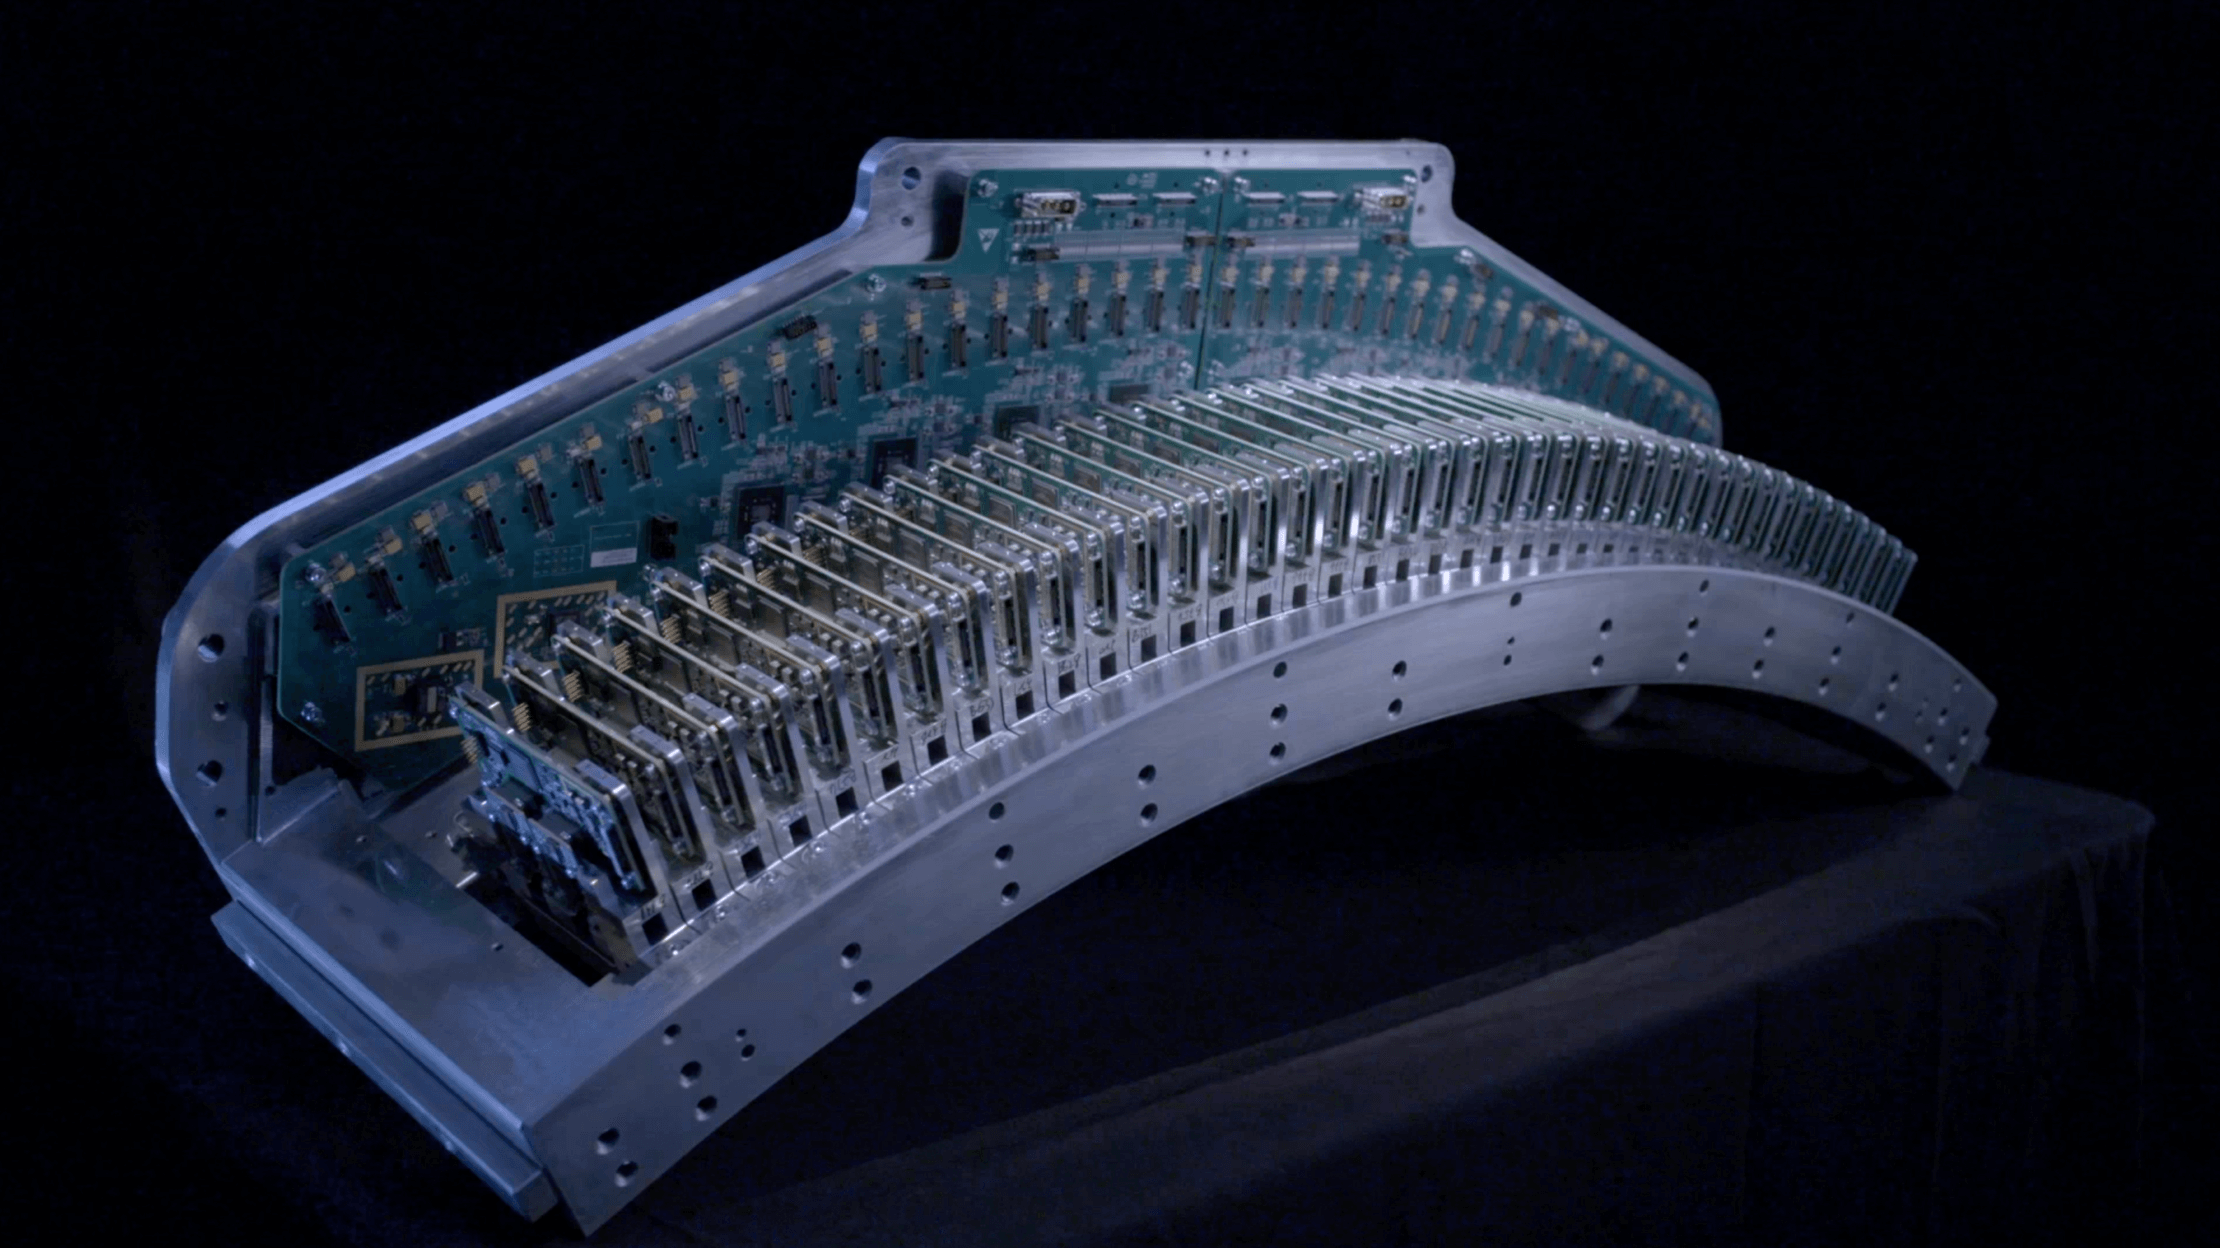

ePhase自由寻心精益算法

自适应冠脉对焦,有效避免搏动伪影

一体化无线心电监测系统

精准捕捉每一次“心动”信号

多扇区冠脉成像

大幅提升心脏扫描成功率